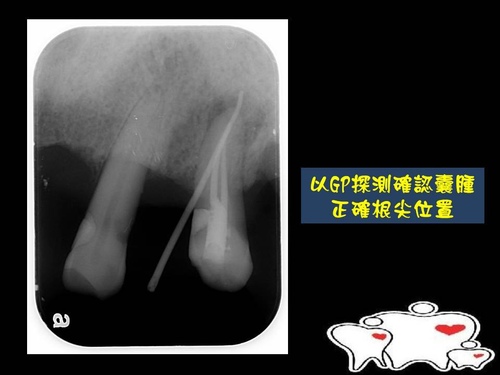

根尖逆充填1.